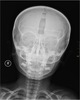

实例:14

地点:PoI-4998-2

大小:15cm x 8cm

笔记:一则可口可乐广告自发地出现在电影童星██████ ████的前额上,该童星现被称为PoI-4998-2。因广告已侵入皮下和脑膜组织,完全移除需经外科手术切除移植。这一事件被迅速发现,因此尚未经历公众曝光和家庭接触。事件导致的容貌变化终止了该童星的演艺生涯。已对外散布有关该童星遭遇摩托车事故的虚假信息。